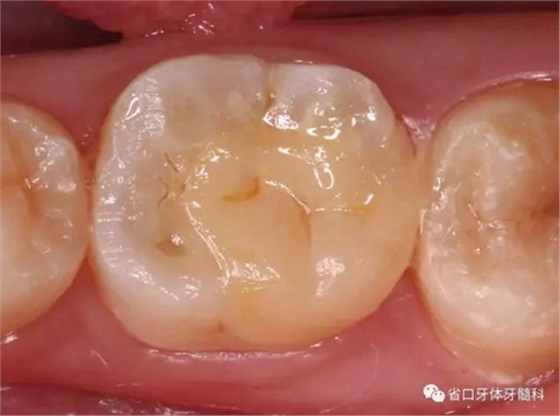

圖7 嵌體粘接后

圖8 嵌體修復后3個月復查